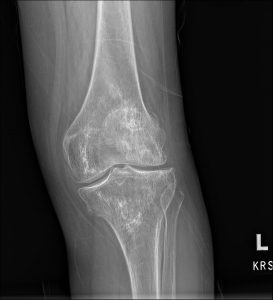

Fig. 1 AP view of the knee